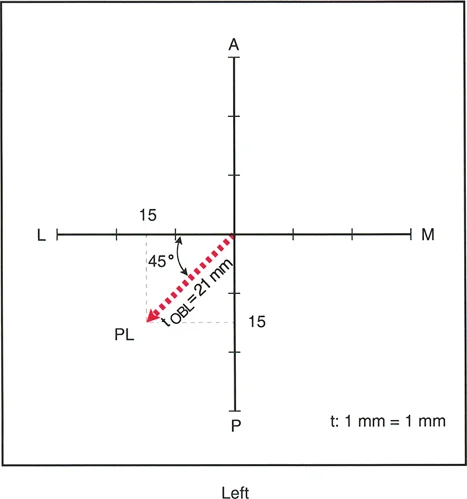

3. الرسوم البيانية للانزياح (Translation Graphs)

يستخدم الأستاذ الدكتور محمد هطيف رسوماً بيانية خاصة لتحليل تشوهات الانزياح، خاصة تلك التي تحدث في المستويات المائلة. هذه الرسوم البيانية تساعد في:

* تحديد الاتجاه الدقيق: مثل الاتجاه الأمامي-الخلفي (AP) أو الإنسي-الوحشي (LAT) أو مزيج منهما (Posterolateral - PL).

* قياس الحجم بدقة: تسمح بقياس حجم الانزياح بالمليمترات، حتى في المستويات المعقدة.

* تحديد مستوى الانزياح: المسافة من المفصل القريب إلى مستوى التداخل.